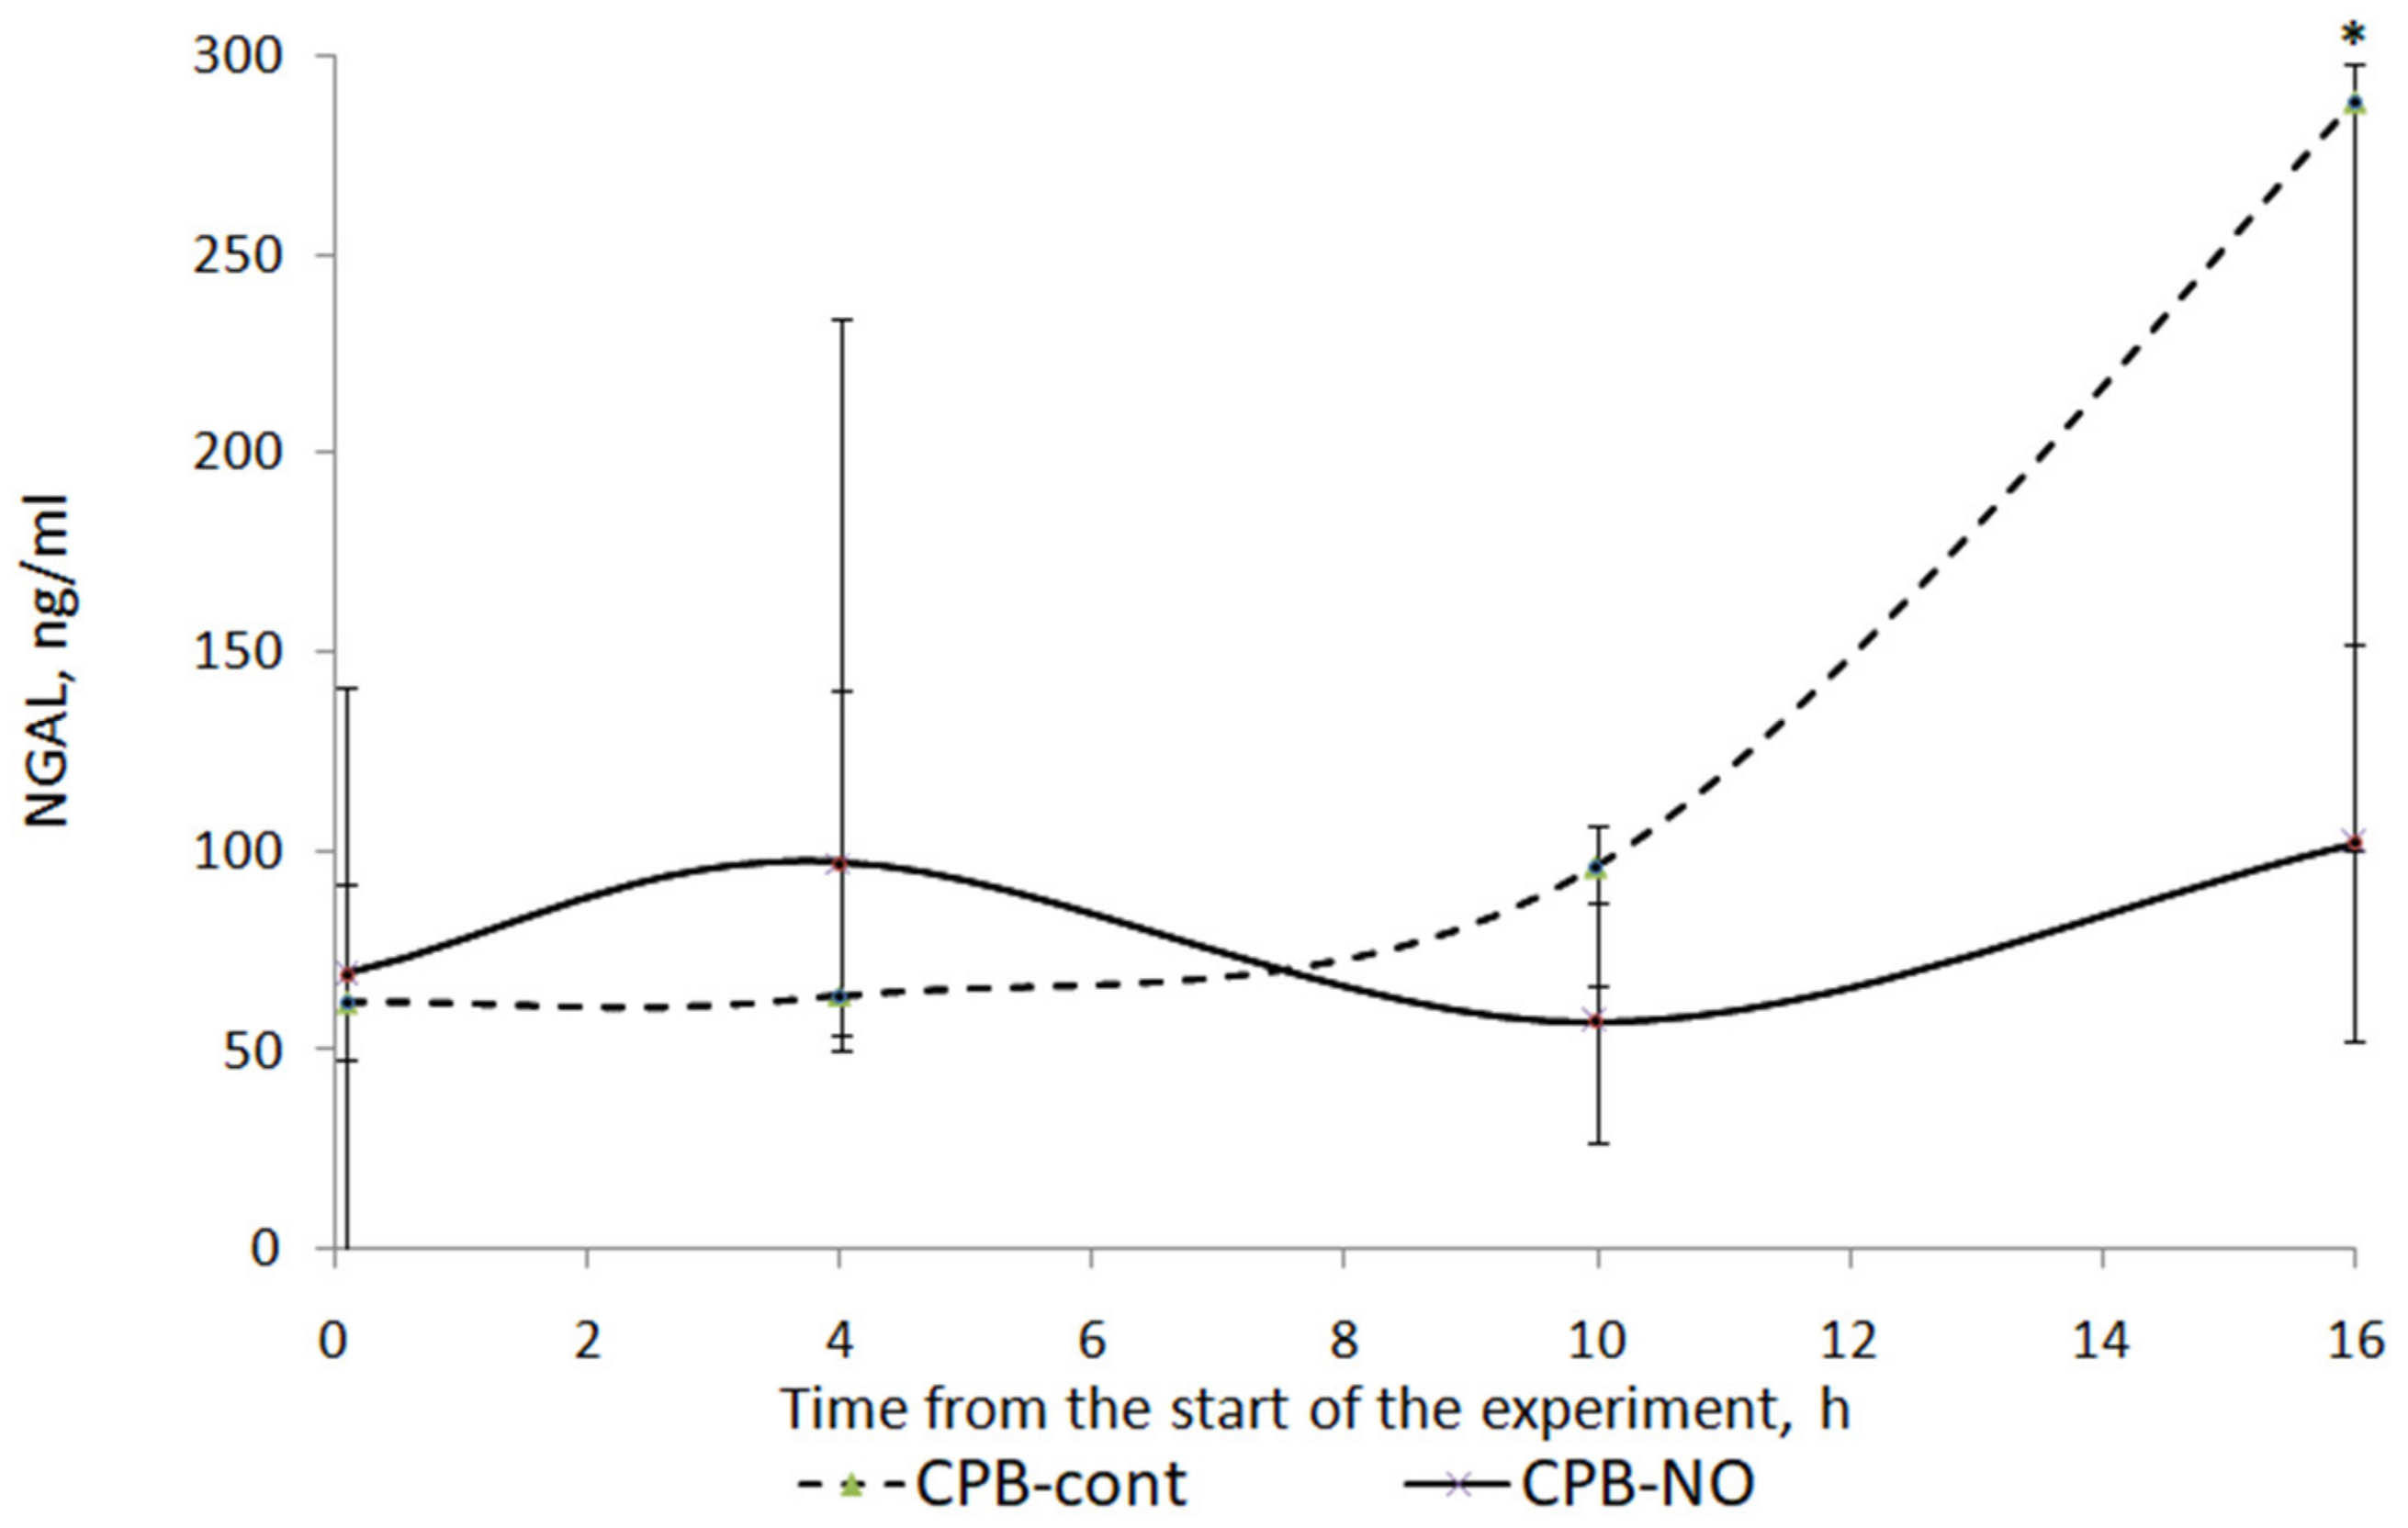

3.3. Renal Function

| Point | CPB-contr, n = 5 | CPB-NO, n = 5 | Mann–Whitney U-Test |

|---|---|---|---|

| Baseline (1) | 62.1 (48.3; 92.8) | 69.4 (43.3; 140.6) | p = 0.77 |

| Weaning CPB (2) | 63.6 (48.2; 234.4) | 96.7 (84.3; 140.1) | p = 0.6 |

| 6 h after CPB (3) | 95.9 (64; 101.7) | 57 (41.8; 87.8) | p = 0.22 |

| 12 h after CPB (4) | 287.9 (100.1; 296.3) | 102 (53.2; 150.9) | p = 0.14 |

| Wilcoxon test | p1–2 = 0.686 p1–3 = 0.345 p1–4 = 0.043 | p1–2 = 0.715 p1–3 = 0.144 p1–4 = 1.000 |